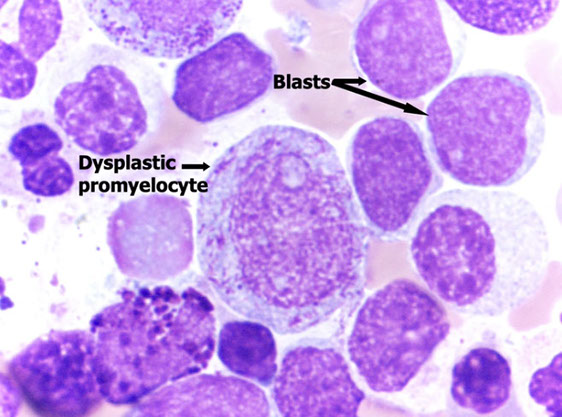

Low power morphologic abnormalities in MDS

Dys-ERYTHRO-poiesis = multinuclear, budding, megaloblastic, karyorhectic nuclei; PAS(+)/vacuoled cytoplasm

Dys-GRANULO-poiesis = small, hypo-/hyperlobated nuclei with hypo- or pseudo Chediak-Higashi granules

Dys-MEGAKC-poiesis = hypo-/non-lobate or multiple, separated nuclei and overall small size

Dysmegakaryopoiesis

Dyserythropoiesis

Dysgranulopoisis

Dysmegakaryopoisis

Meg dysplasia

Granulocytic dysplasia

Erythroid dysplasia [3].